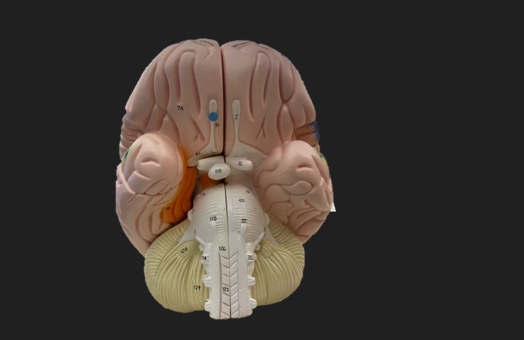

blue dot

olfactory tract

red dot

corpora quadrigemina

dark green dot

cerebral aqueduct

blue dot

cerebral penduncles

pink dot

pons

orange dot

medulla oblongata

yellow dot

mammillary body

dark green dot

pyramids

red dot

olives

blue dot

optic tract

purple dot

midbrain

green dot

folia

orange dot

arbor vitae

yellow dot

fourth ventricle

red dot

vermis

blue dot

hypothalamus

pink dot

cerebral hemispheres

red dot

CN I olfactory

green dot

CN II optic

pink dot

CN III oculomotor

orange dot

CN IV trochlear

blue dot

CN V trigeminal

purple dot

CN VI abducens

green dot

CN VII facial

green dot

CN VIII vestibulocochlear

red dot

CN IX glossopharyngeal

CN X vagus

orange dot

CN XI spinal accessory

pink dot

CN XII hypoglossal